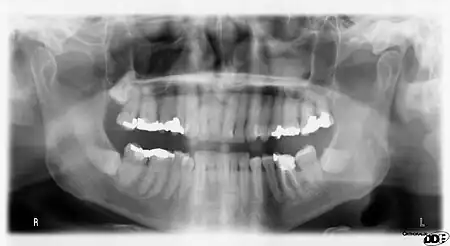

Dental radiographs, commonly known as X-rays, are radiographs used to diagnose hidden dental structures, malignant or benign masses, bone loss, and cavities.

A radiographic image is formed by a controlled burst of X-ray radiation which penetrates oral structures at different levels, depending on varying anatomical densities, before striking the film or sensor. Teeth appear lighter because less radiation penetrates them to reach the film. Dental caries, infections and other changes in the bone density, and the periodontal ligament, appear darker because X-rays readily penetrate these less dense structures. Dental restorations (fillings, crowns) may appear lighter or darker, depending on the density of the material.

It is possible for both tooth decay and periodontal disease to be missed during a clinical exam, and radiographic evaluation of the dental and periodontal tissues is a critical segment of the comprehensive oral examination. The photographic montage at right depicts a situation in which extensive decay had been overlooked by a number of dentists prior to radiographic evaluation.

Panoramic films

Panoramic films are extraoral films, in which the film is exposed while outside the patient's mouth, and they were developed by the United States Army as a quick way to get an overall view of a soldier's oral health. Exposing eighteen films per soldier was very time consuming, and it was felt that a single panoramic film could speed up the process of examining and assessing the dental health of the soldiers; as soldiers with toothache were incapacitated from duty. It was later discovered that while panoramic films can prove very useful in detecting and localizing mandibular fractures and other pathologic entities of the mandible, they were not very good at assessing periodontal bone loss or tooth decay.[18]